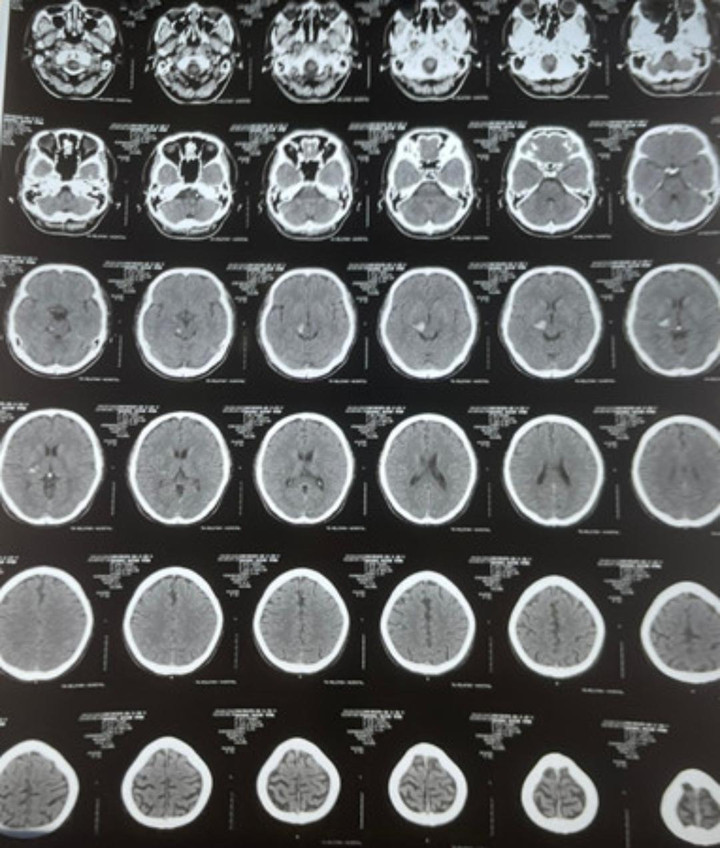

Phim chụp CT của bệnh nhân Nguyễn Văn Anh, 35 tuổi, ngụ quận 8, TP.HCM. (Ảnh BVCC)

BS Mạnh Hà chia sẻ về trường hợp bệnh nhân Nguyễn Văn Anh, 35 tuổi (ngụ quận 8) đã hồi phục gần như hoàn toàn sau 7 ngày điều trị tại bệnh viện.

Bệnh nhân có thể trạng béo phì, cao huyết áp, rối loạn lipid máu không điều trị thường xuyên, được các bác sĩ Bệnh viện Quân y 7A, TP.HCM thăm khám và chụp CT sọ não chẩn đoán xuất huyết khối não đồi thị phải.

"Lúc 22h bệnh nhân xuất hiện các triệu chứng đau đầu, chóng mặt, tê và yếu nửa người trái, khoảng 22h30 bệnh nhân đã được người nhà đưa đi cấp cứu kịp thời. Tại bệnh viện, các bác sĩ tiến hành điều trị tích cực, kiểm soát tốt huyết áp, đường huyết, nhiệt độ, để lại di chứng là tê bì nhẹ ở tay trái", BS Mạnh Hà nói.